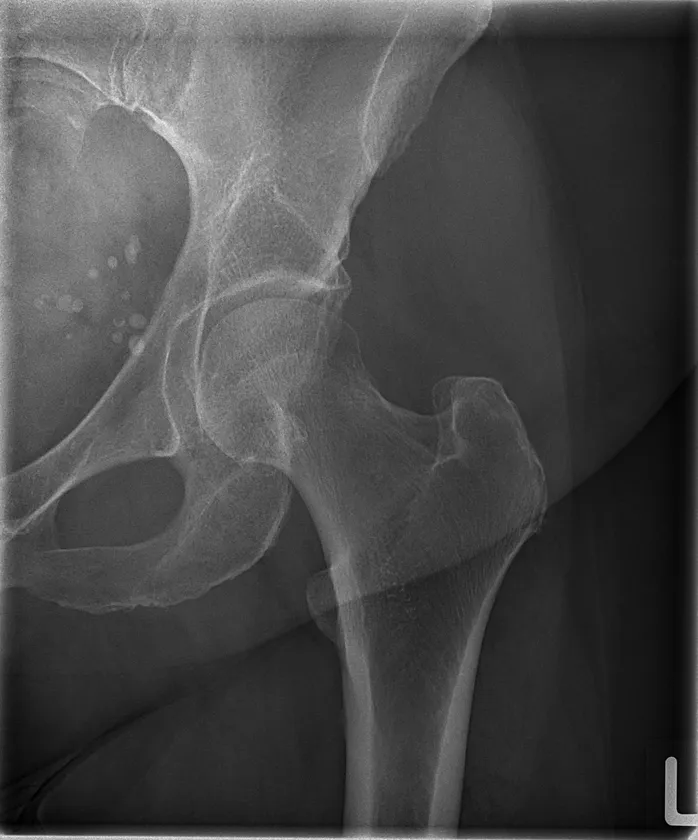

4. 高精細画像技術の展示

最大1.3kWの高出力に加え、最新のノイズ低減技術との融合により実現した高精細な画像描写をご覧いただけます。診断精度の向上に直結する画像品質の進化を、実際の撮影画像でご確認ください。

TRB 9020Hで撮影した大腿骨レントゲン写真

※84 kV HP mode 1.8 mAs, 0.12 sec Exposure Index: 367